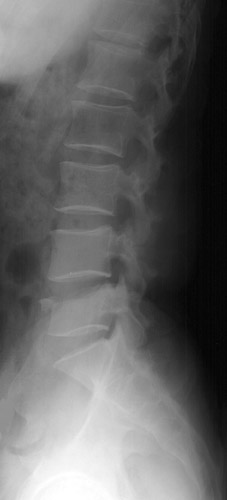

Look for the compression fractures in the radiographs below. Can you find them?

Click on the image for the answer.

Lateral view